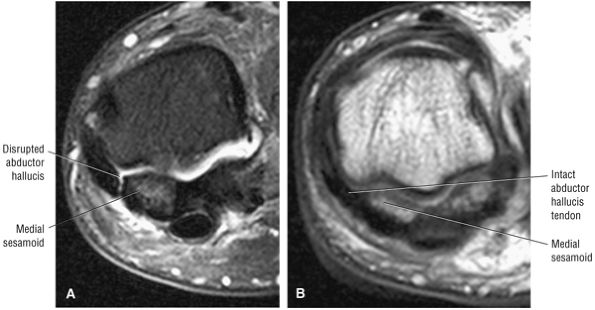

The muscles of the foot are the extensor digitorum brevis (Fig. 5.14), the abductor hallucis (Fig. 5.15), the flexor digitorum brevis (Fig. 5.16), the abductor digiti minimi (Fig. 5.17), the quadratus plantae (Fig. 5.18), the lumbricals (Fig. 5.19), the flexor hallucis brevis (Fig. 5.20), the adductor hallucis (Fig. 5.21), the flexor digiti minimi brevis (Fig. 5.22), the dorsal interossei (Fig. 5.23), and the plantar interossei muscles (Fig. 5.24).